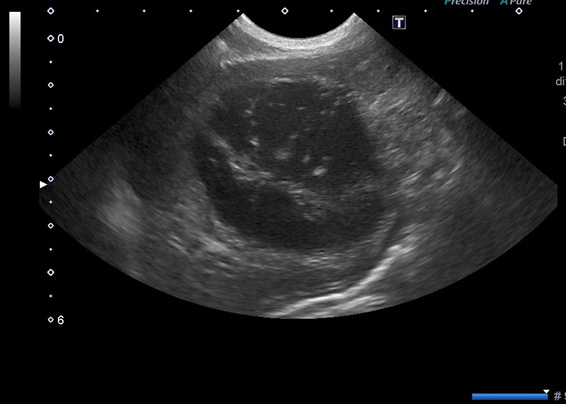

胆嚢粘液嚢腫